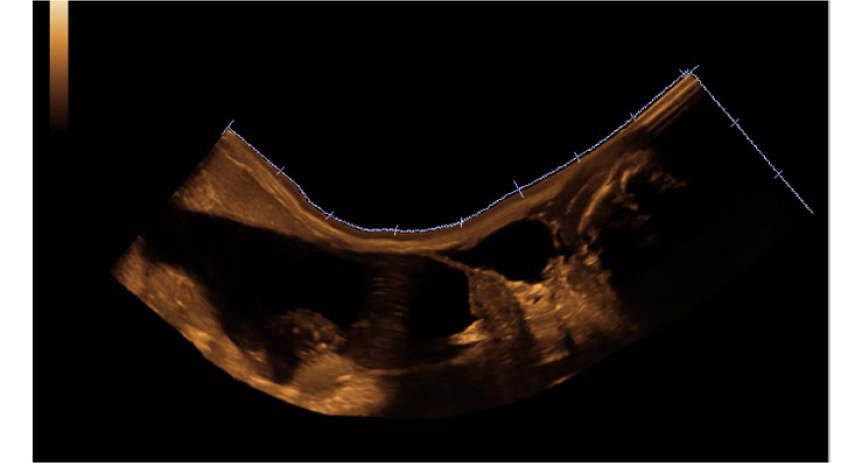

Galería de imágenes

Galería de imágenes